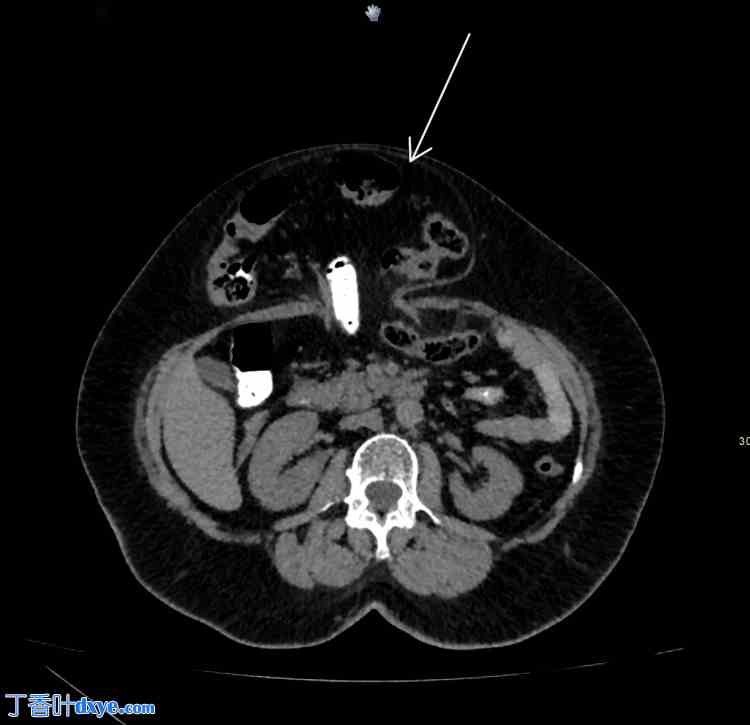

CT扫描(图1、图2)显示一个51毫米×36毫米的大型中线前腹壁缺损,伴有部分横结肠和大网膜疝出。鉴于疝气的症状性以及缺损处存在腹壁内容物,认为有必要进行手术干预以防止进一步的并发症。

图1. 口服造影剂的非造影CT扫描显示疝囊内肠管的轴向视图(箭头)。